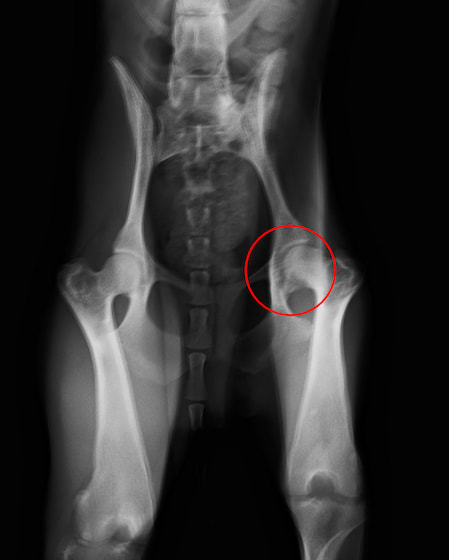

大体骨頭壊死症(レッグ・ペルテス病)(2024/07/09)

大腿骨の先端(大腿骨頭)への血液の供給が上手くいかない事で変形や壊死を起こしてしまう股関節の疾患です。主に4ヶ月齢〜1歳未満の、成長期の小型犬で発症することが多いと言われています。後ろ足を庇うように歩いたり、痛みで足を挙げるようになったり、その結果として筋肉が痩せ細ったりして、上手く歩けなくなってしまいます。触診やレントゲン検査などを用いて診断し、多くの場合は大腿骨頭を切除する外科的な治療を行います。少しでもワンちゃんの歩き方に違和感を感じた場合は、お早めにご相談下さい。

獣医師 雨ヶ崎